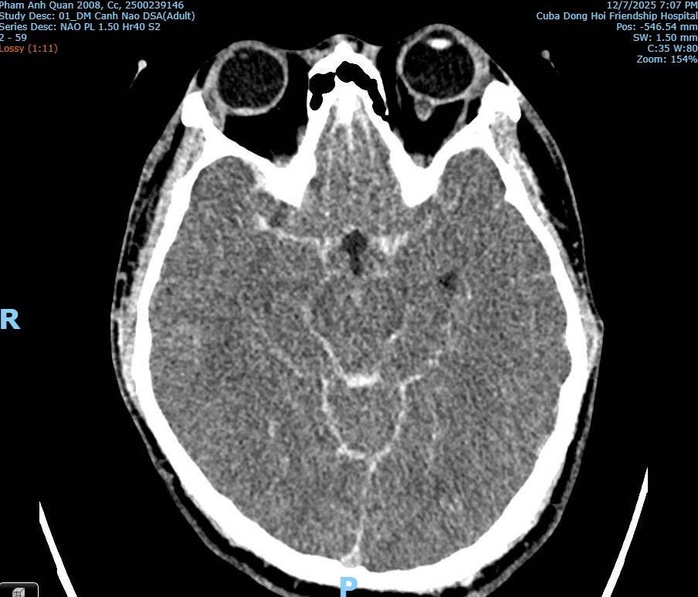

Hình ảnh CT/MRI: Xuất huyết dưới nhện do vỡ phình mạch máu não của bệnh nhân Phạm Anh Q. thời điểm tại Bệnh viện Hữu nghị Việt Nam - Cuba Đồng Hới

Phân tích từ hình ảnh chẩn đoán, bác sĩ Hùng cho biết không phát hiện tổn thương xương cột sống cổ, không có tổn thương vòm sọ, không có tổn thương não do lực tác động bên ngoài. Đồng thời chỉ ghi nhận xuất huyết não lan tỏa và phù não, điển hình của vỡ phình mạch não.

Bác sĩ Hùng khẳng định theo hình ảnh chuyên môn y khoa từ chẩn đoán thì không có dấu hiệu nào cho thấy nạn nhân bị đánh với lực đủ mạnh để gây gãy cổ hoặc chấn thương sọ não do tác động ngoại lực.